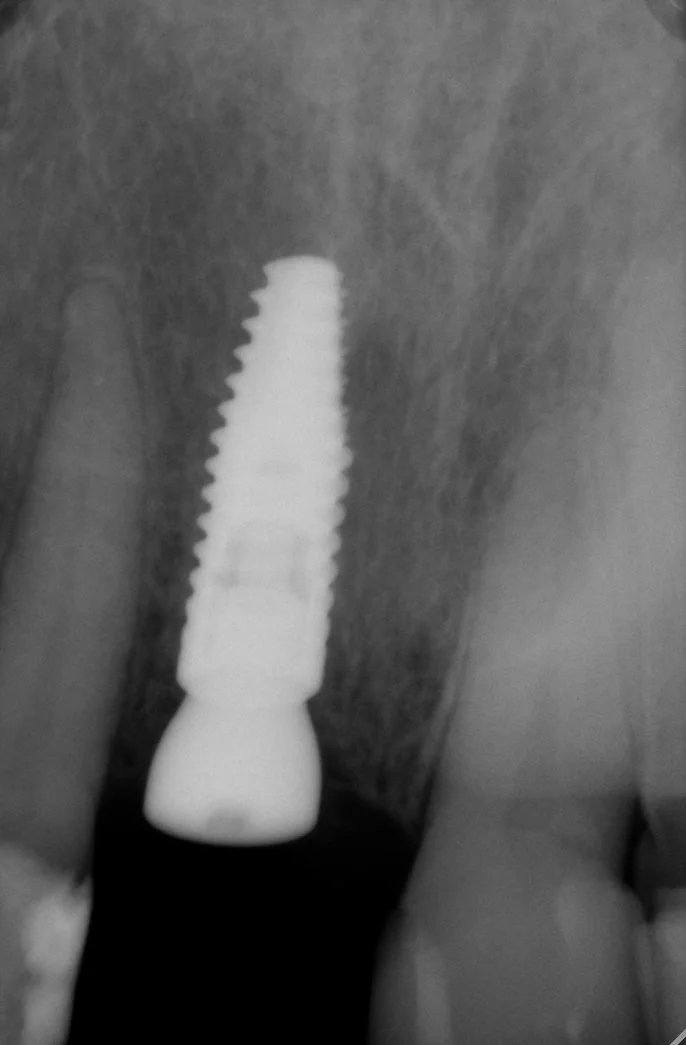

This 60 year old lady had recurring problems with the top right crowned front tooth which was restored with a gold post crown. This post was short and angled and the post crown kept on debonding from the root and the post crown kept falling out of her mouth. Eventually decay ensued and the root cracked as illustrated in the radiograph.

-

The patient was referred to me in 2021 at Lismore and I referred the patient to a Periodontist in Brisbane. He extracted the tooth, placed a temporary partial denture plate to fill the space and subsequently placed a Straumann implant fixture and healing cap

I completed this case at Lismore in 2022 and this radiograph illustrates the completed the screw accessible zirconia implant crown